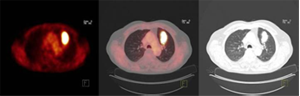

Beispiel 1: Lungenherd